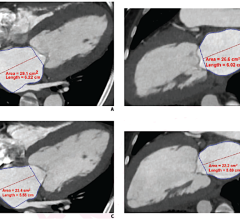

Based in Edinburgh, Scotland, Barco’s Advanced Visualization (AVIS) group is specialized in 3D clinical software solutions, marketed worldwide under the product names ‘Voxar 3D’ and ‘Voxar 3D Enterprise.’ As part of the agreement, TMVS will become the new owner of all AVIS assets, including its full product portfolio. TMVS will help support the development of 3D volume rendering and advanced visualization capabilities for all Toshiba modalities.